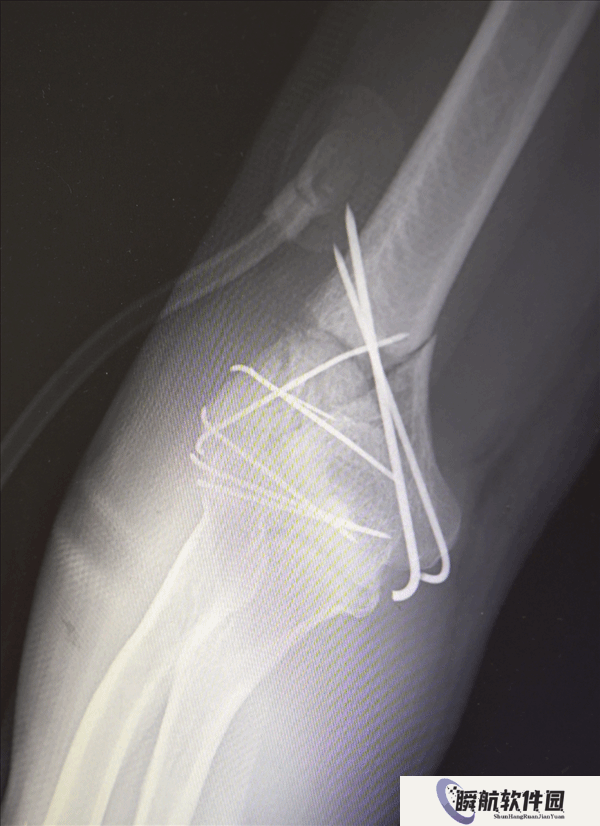

鉴于男子多处骨折,其中最严重的当属右肘部C3型粉碎性骨折,关节面及髁上严重粉碎(碎成了七块),肘关节易粘连,复位固定难度极高。

最终医疗团队采用了“拼古董”式复位固定技术,就像修复一件珍贵的古董瓷器,先拼接大块骨块再贴合小块,先后进行了两次手术。